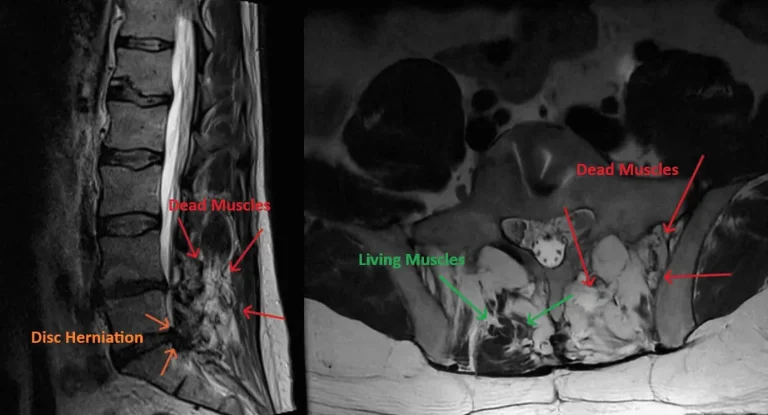

Muscle Destruction

MRI of lumbar spine showing recurrent disc herniation post discectomy highlighted by arrows.

Recurrent Herniation

Recurrent Disc Herniation

20-30% recurrence rate as disc material herniates through the same untreated annular tear, requiring repeat surgery.